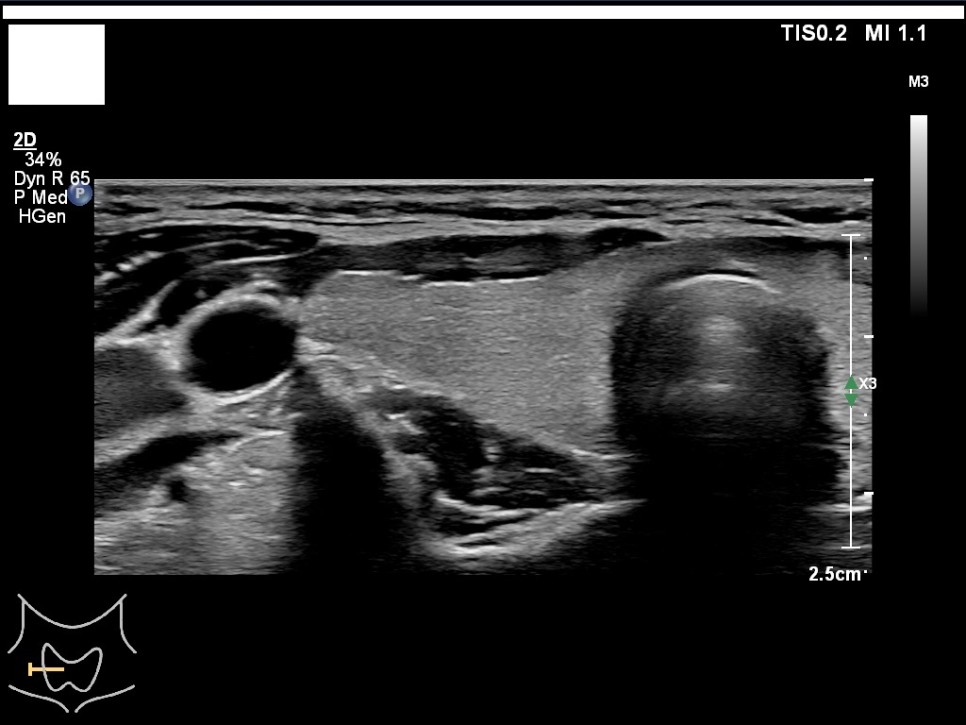

갑상선, 부갑상선 초음파 검사 급여 기준 1. 표준 영상의 범위 모든 영상에는 경부의 해부학적 위치(모식도나 문자)를 표기하여야 한다.

A) 병변이 없는 경우: 우엽 중부 가로 스캔, 우엽 중앙부 세로 스캔, 협부 가로 스캔, 좌엽 중부 가로 스캔, 좌엽 중앙부 세로 스캔, 우경부 림프절, 좌경부 림프절 나) 병변이 있는 경우: 병변이 없는 경우의 표준 영상과 함께 병변 부위에서 2개의 수직 관계 단면 영상(횡단/종단) 및 병변의 크기가 측정된 경우: 병변이 없는 경우의 표준 영상

좌측 경부 림프절 / 중심 경부 림프절 / 협부 옆 스캔 2. 판독 소견서가) 등록 번호, 성명, 생년월일 또는 연령, 성별, 검사명, 검사 일시, 판독 일시, 검사와 판독한 의사(면허 번호), 의료기관명, 검사 소견 및 결론 나) 검사 소견에는 갑상선 에코, 병변의 유무를 기술하여야 한다. 결절이 있을 경우 위치, 최대지름, 주요 소견, K-TIRADS의 내용을 기술하여야 하며, 암으로 진단된 결절을 추적할 경우 위치, 3방향 직경, 주요 소견, 전 검사와 변화 여부, 경부 림프절의 평가 및 이상 소견 여부를 기술하여야 하며, 경부 림프절에 이상이 있을 경우 위치, 크기, 주요 소견을 기술하여야 한다. 결절이 여러 개 있을 경우 암 위험도에 따라 선택적으로 기술할 수 있다. 또 소아 등에서의 환자의 협력도 음창 등이 좋지 않아 표준 영상 획득에 제한이 있는 경우 추가 기술해야 한다.